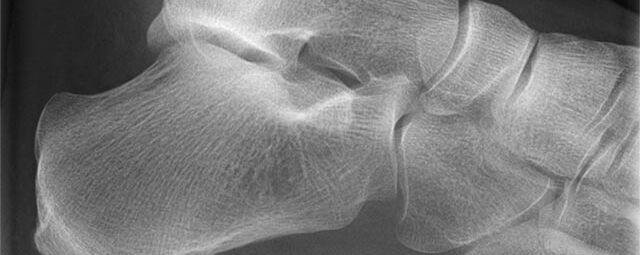

Konventionelles Röntgen

Der Begriff Röntgen, oder auch Röntgendiagnostik bezeichnet ein Verfahren in der Radiologie, bei dem von einer Röntgenröhre elektromagnetische Wellen (Röntgenstrahlen) durch die zu untersuchende Körperregion des Patienten gesendet werden. Je nach Dichte der Gewebeart des Körpers (z.B. Knochen oder Lunge) werden die Röntgenstrahlen im Körper unterschiedlich stark abgeschwächt. Ein digitaler Detektor empfängt dann die Röntgenstrahlen, die in abgeschwächter Form den Körper wieder verlassen haben. Daraus wird das Röntgenbild erzeugt.

Die zu untersuchenden Anteile des Körpers werden meistens

in 2 unterschiedlichen Projektionsebenen dargestellt.

In einigen Körperregionen sind spezielle Zielaufnahmen notwendig.